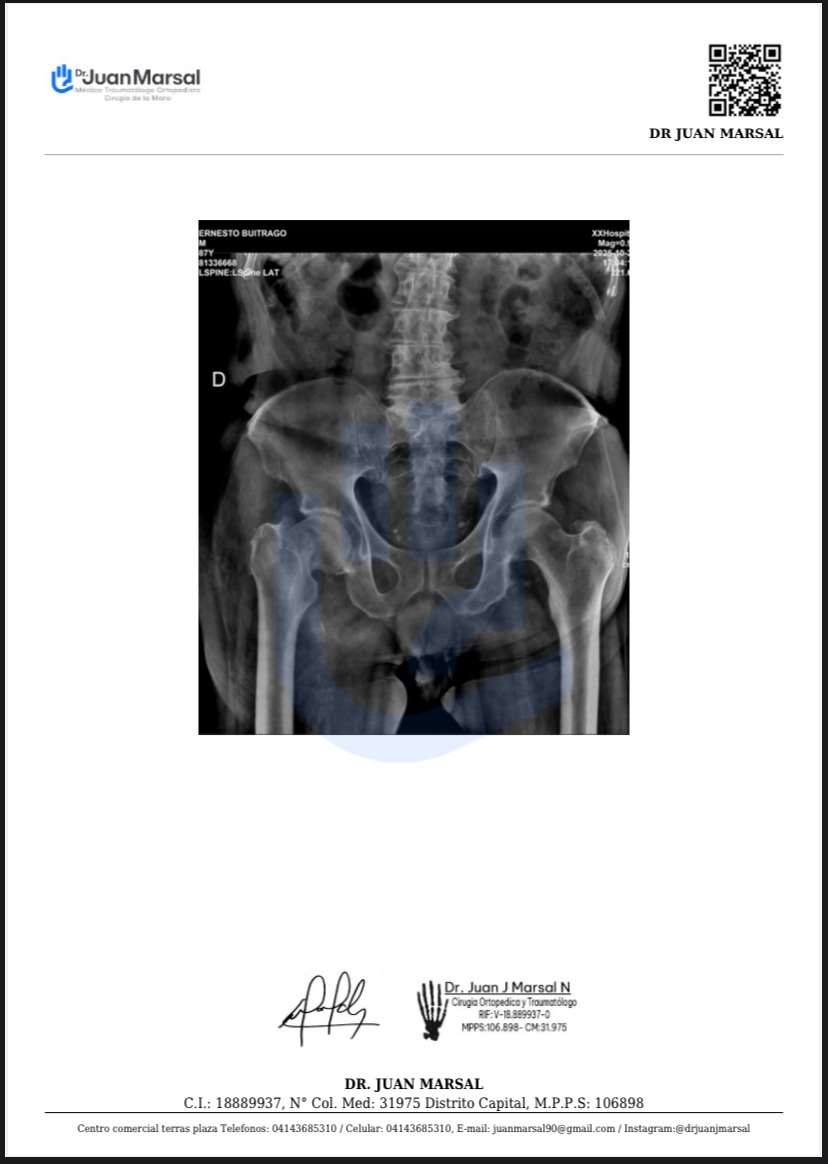

Mi nombre es Andres Buitrago y recurro a su ayuda para poder cubrir los gastos de una cirugía urgente para mi papá, quien sufrió una fractura intracapsular transcervical de fémur derecho a sus 87 años. Los médicos indicaron que necesita una cirugía de hemiartroplastia de cadera derecha con prótesis de Thompson cementada, procedimiento que lamentablemente no puedo costear.